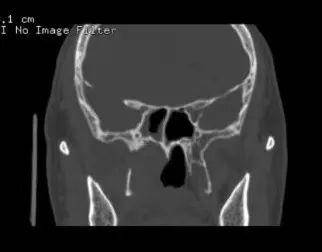

病例1:患者男,56岁,因反复鼻出血入院,入院CT、MRI示肿瘤侵犯右侧翼腭窝、颞下窝、翼突根及翼内外板。入院诊断:侧颅底恶性肿瘤。肿瘤范围大,难度大,风险高。

CT、MRI示肿瘤侵犯右侧翼腭窝、颞下窝、翼突根及翼内外板